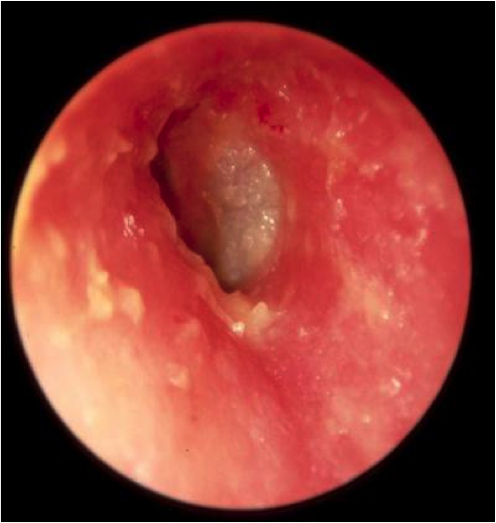

Bullous Myringitis

→infection that causes painful blisters on the eardrum (tympanum)

Sudden onset of pain, Usually NO fever

PE: TM Inflammation w/ blebs

Tx: Analgesics, abx w/ AOM, Macrolides